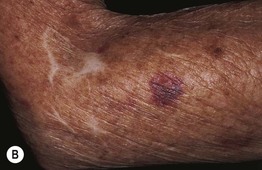

Fig. 18.1 Clinical examples of petechiae and purpura. A Round to oval petechiae, ≤3 mm in diameter. B Actinic (solar) purpura and pseudoscars, both in sites of actinic damage plus trauma. C Non-inflammatory (bland) retiform purpura as well as hemorrhagic bullae in a patient with disseminated intravascular coagulation (DIC). D Palpable purpura due to cutaneous small vessel vasculitis (inflammation plus hemorrhage). A, Courtesy, Warren Piette, MD; B, Courtesy, Jean L. Bolognia, MD; C, Courtesy, Judit Stenn, MD.

– Ecchymoses: usually >1 cm and macular with round/oval to slightly irregular borders, and typically have an element of trauma in their pathogenesis (see Table 18.1; Fig. 18.1B); a greater volume of hemorrhage leads to a hematoma, which is palpable.